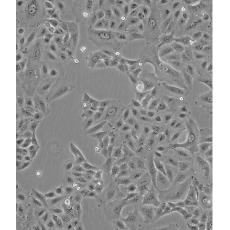

產(chǎn)品名稱 A549/DDP

中文名稱 人肺腺癌耐順鉑株

生長特性 adherent

形態(tài)特征 epithelial